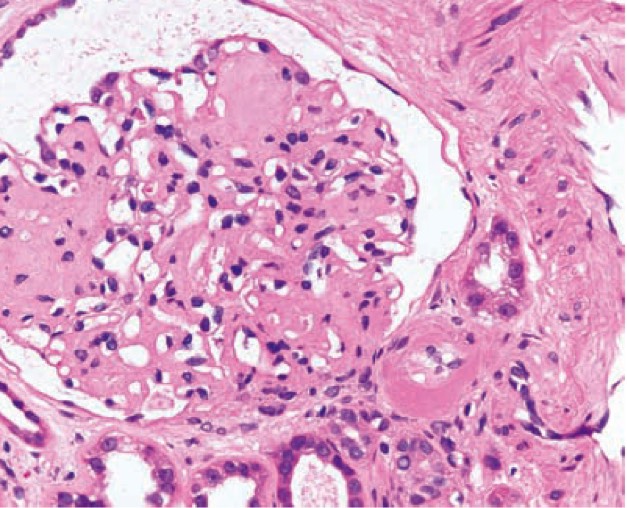

1009. На микрофотографии приведены данные биопсии почки пациента с микроальбуминурией, диагноз